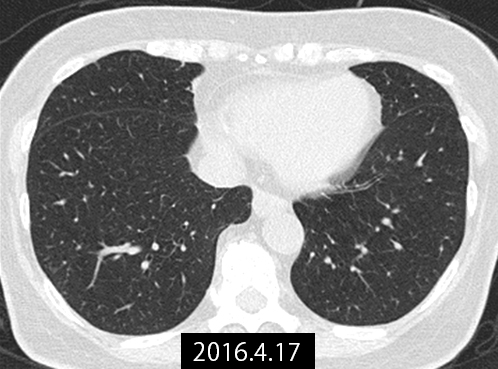

CT画像で見る治療経過

転移巣の治療経過

治療前のCT(図1)では左右両葉に多発肺転移を認めました。当初本人が化学療法を拒否されていたことから、不正性器出血を制御する目的で原発巣(子宮)のみに対し放射線治療を行う方針としました。放射線治療前に成分採血を行い、WT1樹状細胞ワクチンの作成を実施しました。

本症例では、原発巣への限定的な放射線治療と、規定量以下の化学療法、そしてWT1樹状細胞ワクチン療法を組み合わせる治療を行いました。このような治療の組み合わせと順序により、多発肺転移巣の縮小が確認されました(図2)。

図2:2016年4月 治療後の肺転移巣